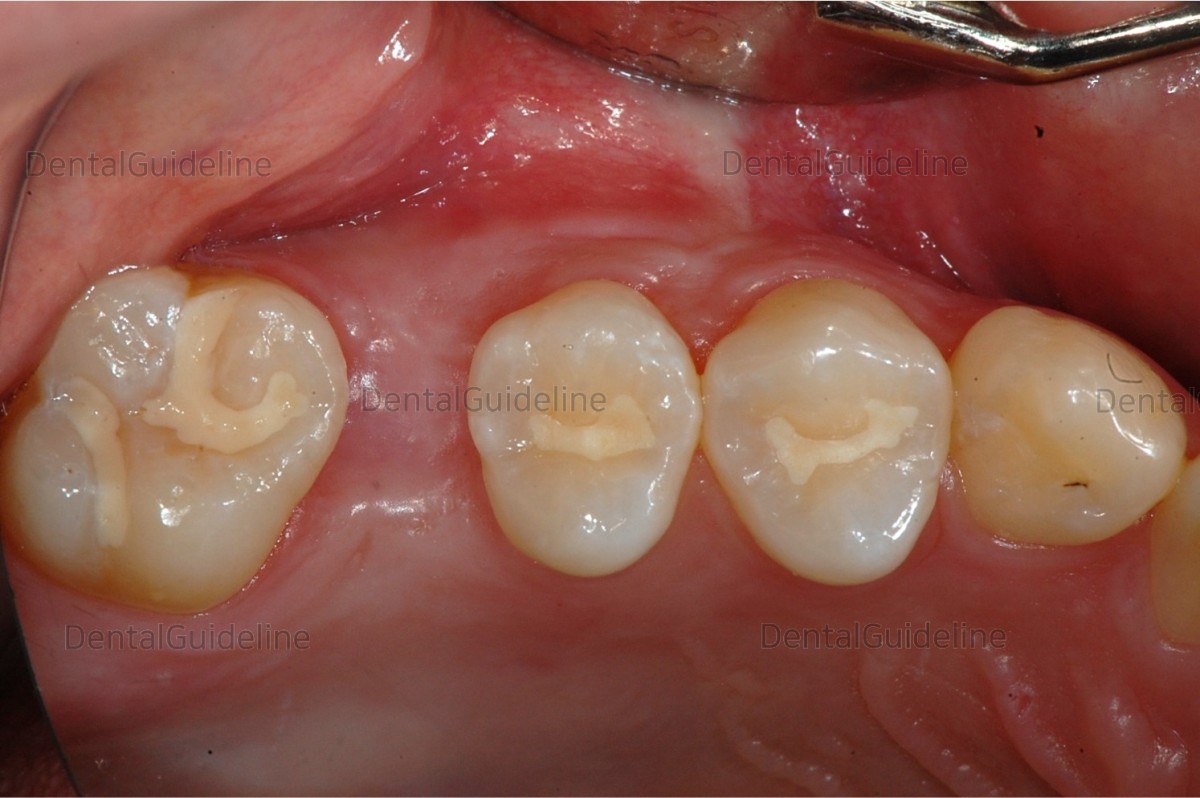

![]()

20. HA was connected by extending the gingiva from a small size

to an appropriate size.

21. Impression taking.

22. Custom abutment was connected.

23. Zirconium crown.